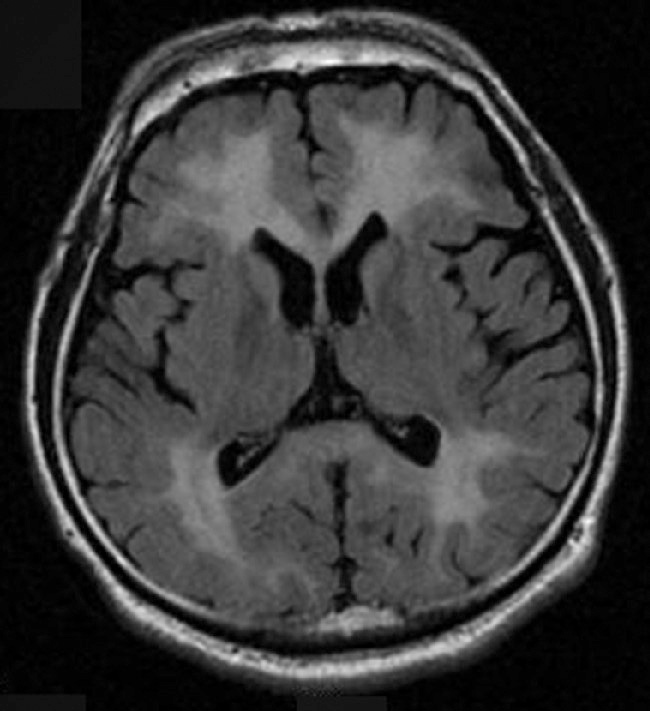

ⅴ) MRI (遅発性脳症): 典型的にはMRI (T2強調画像,拡散強調画像,FLAIR画像) では脳室周囲の大脳白質および半卵円中心に両側・びまん性・合流性の高信号域が認められる (図2).